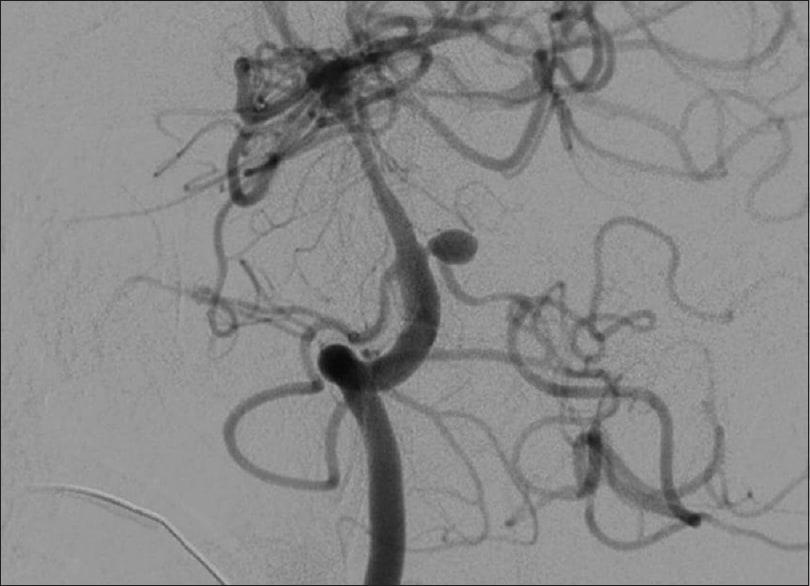

Kỹ thuật chụp DSA còn thường được dùng để chẩn đoán một loạt các bệnh mạch máu, như tắc nghẽn trong lòng động mạch hay tĩnh mạch, phình động mạch não (đặc biệt là phình động mạch nội sọ), xuất huyết mạch máu, dị dạng động – tĩnh mạch và nghiên cứu hệ thống mạch máu của khối u ác tính (ung thư).

Nguồn: Asian Journal of Neurosurgery